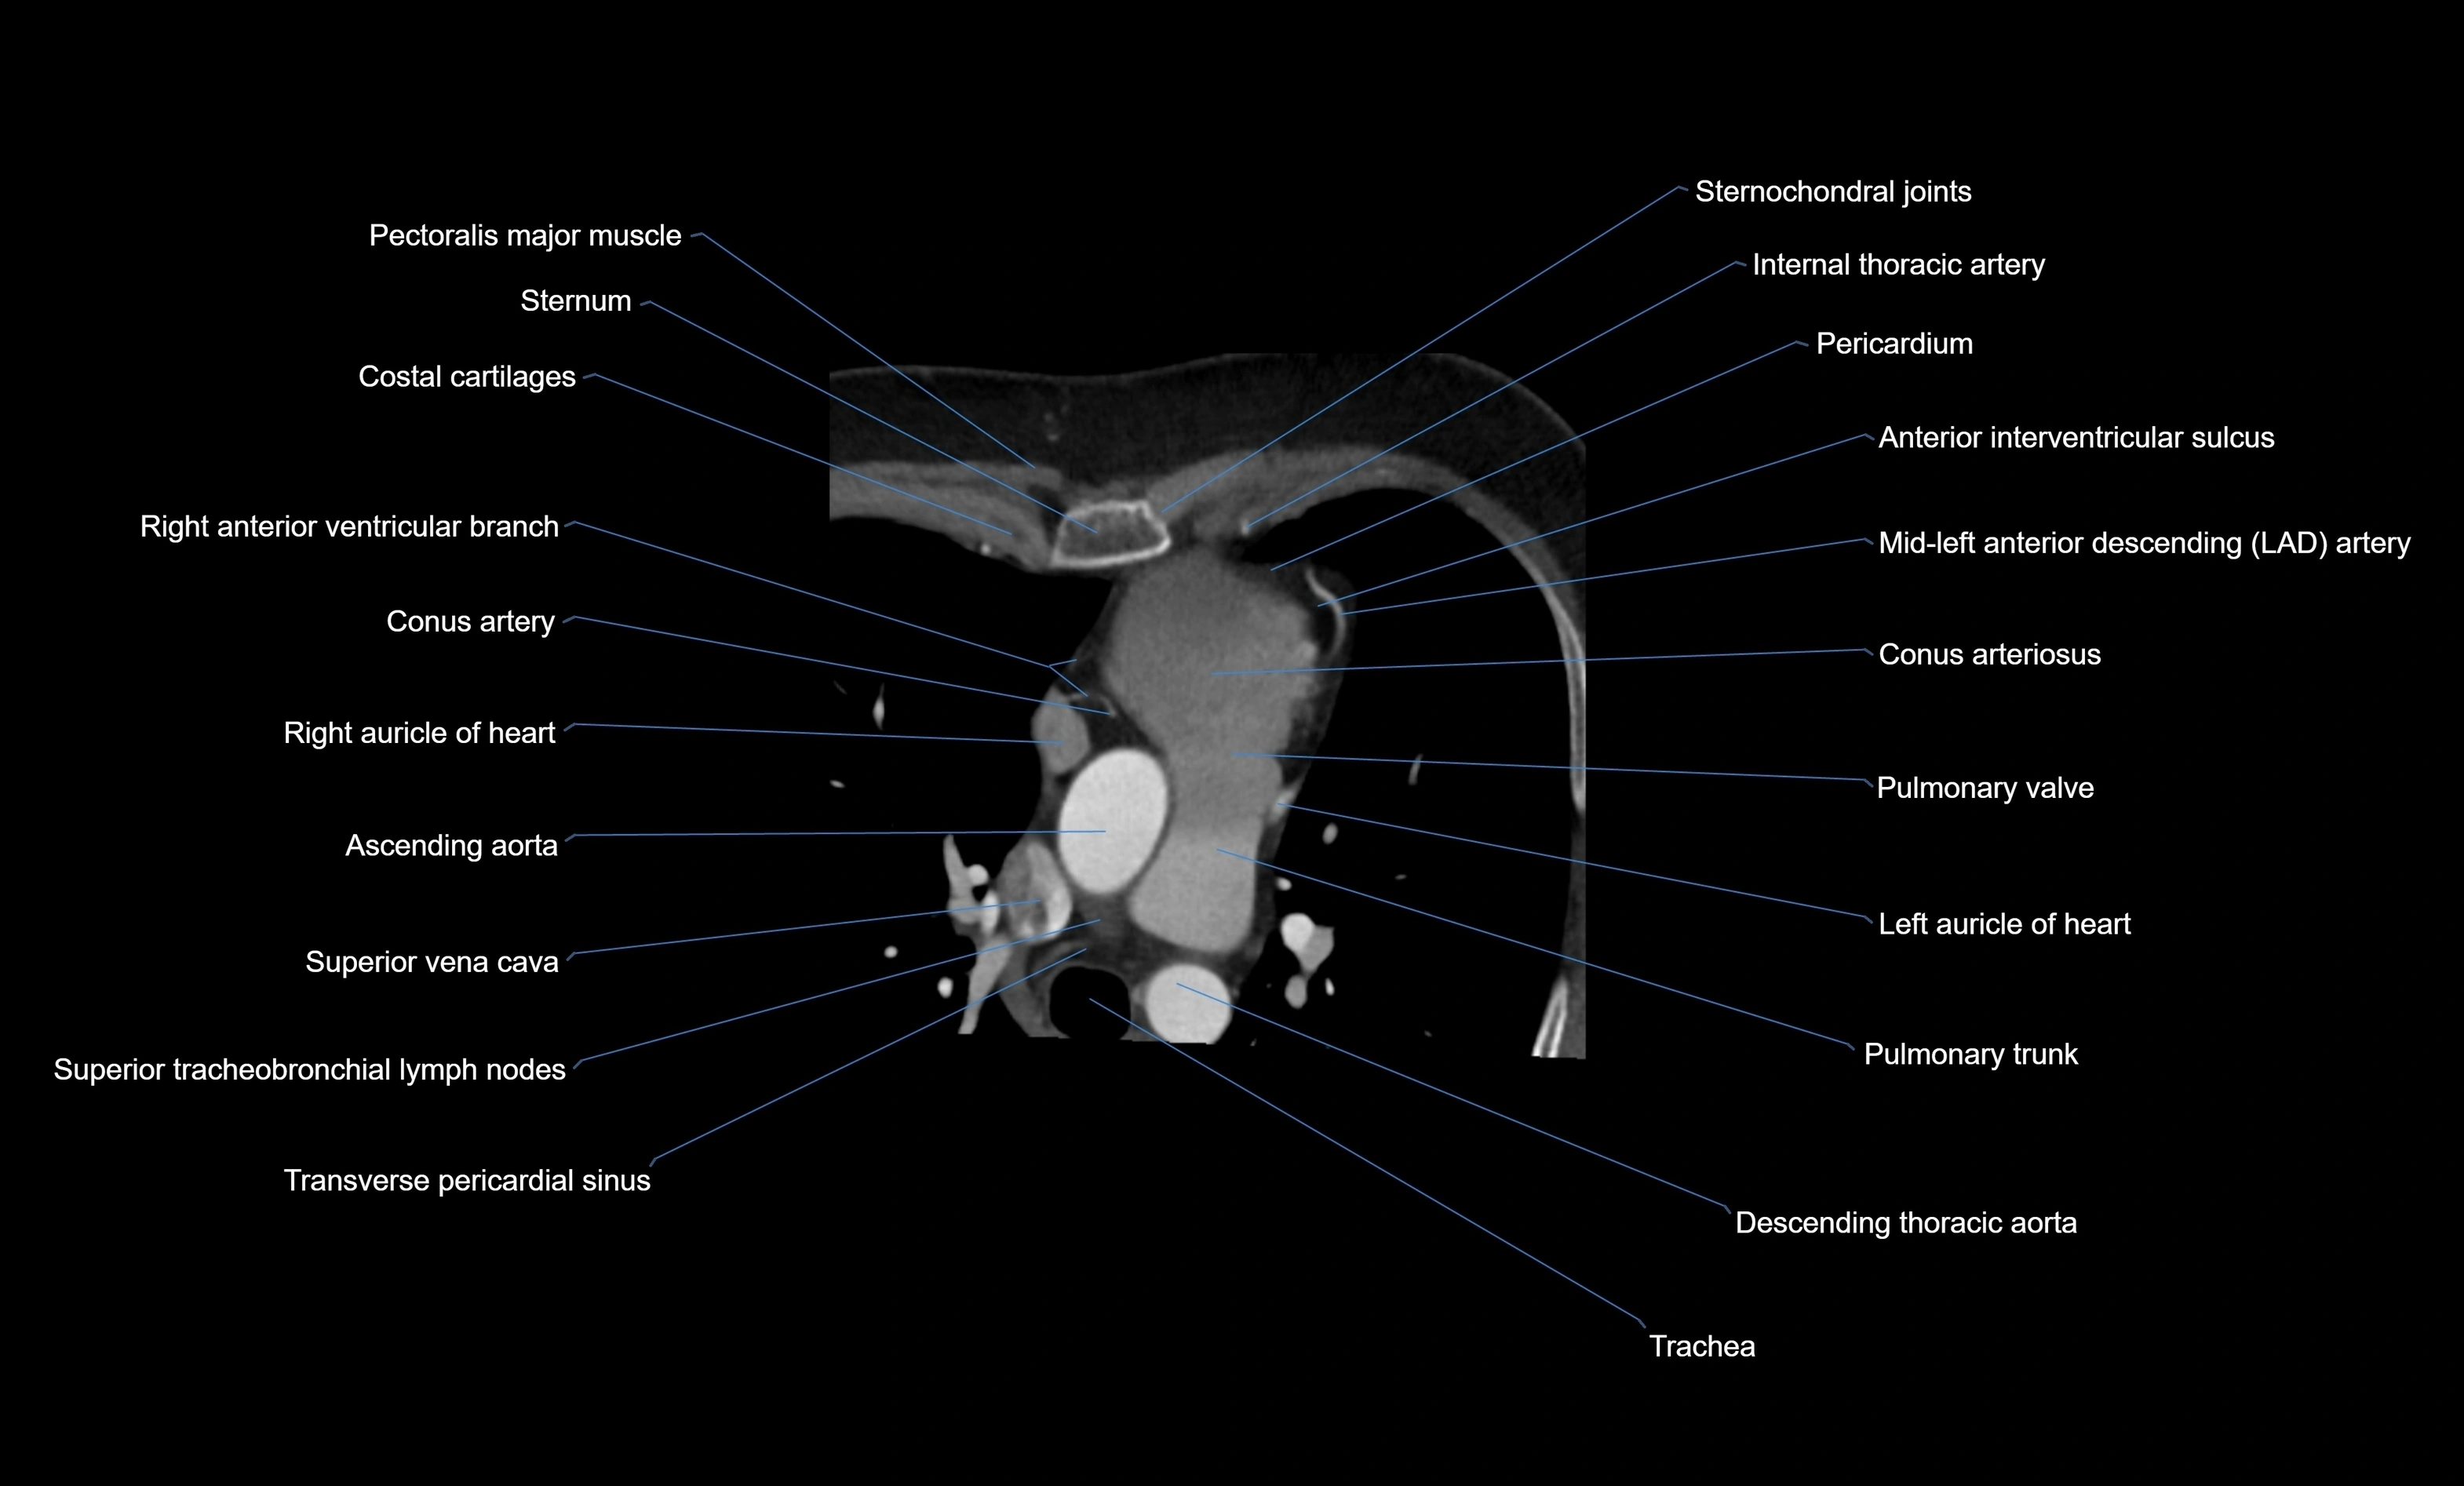

CT images